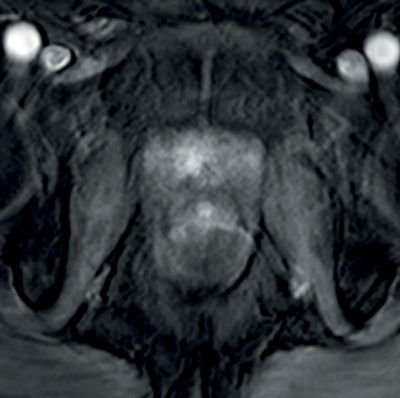

Transitional and central zone tumours are more difficult to evaluate using conventional T1 and T2WI as both normal and cancerous tissues in these areas demonstrate low signal intensity. Additionally, the normal central gland is commonly heterogeneous, making delineation of abnormal areas challenging. DWI may improve the detection and localisation of central / transitional zone tumours, as they also demonstrate restricted diffusion. Studies have shown that transitional zone tumours have lower ADC values than normal gland as well as BPH nodules [5,6] (Figure 2). The sensitivity for tumour detection in the transitional zone, however, still remains less than in the peripheral zone [5].

Figure 2a: Axial T2WI with low signal in the right central zone.

Figures 2b and 2c: DWI and ADC map confirm restricted diffusion at the site of tumour.